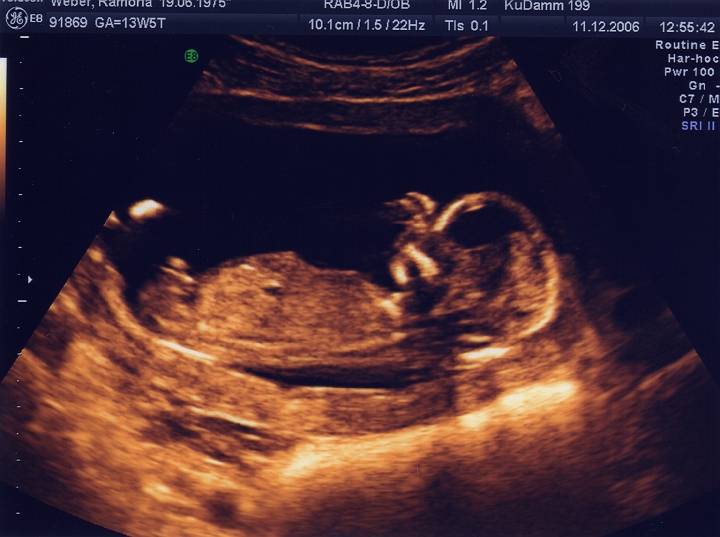

14. SSW - 10 cm lang